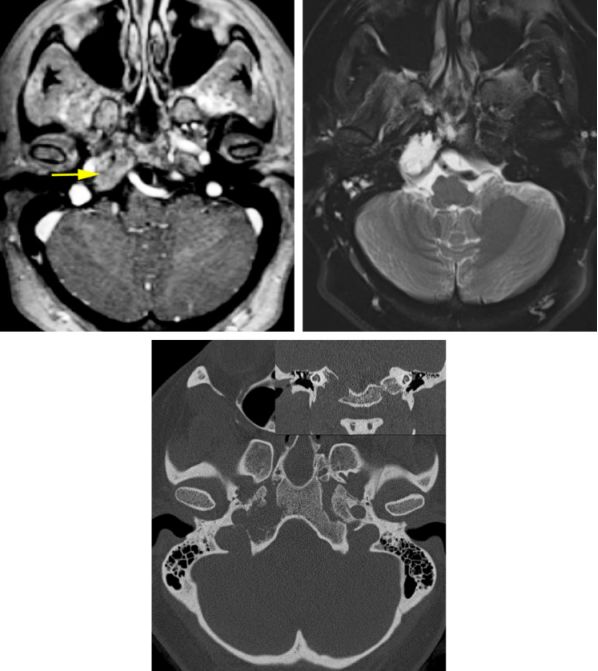

术前评估

可疑颅底脊索瘤的检查方法包括磁共振成像(MRI)和计算机断层扫描(CT)。病变累及海绵窦时尤其要注意Ⅲ-VI颅神经。

脊索瘤和软骨肉瘤在MRI影像表现上难以区分,病变在T1加权相上与灰质相比表现为等低信号,在T2加权相表现为高信号,增强相常稍有强化。脊索瘤内常因瘤内出血有含铁血黄素或铁蛋白沉积。颅底高分辨率CT可以显示周围正常及受侵犯骨质解剖、瘤内钙化以及周围骨质破坏的程度。也能判断肿瘤是否包绕岩骨段颈内动脉或使其狭窄。

图14:图为前颅底巨大软骨肉瘤。矢状位CT显示肿瘤侵袭周围骨质的程度(上图)。经双侧额下入路(中图)联合内镜经鼻入路切除肿瘤。蓝色箭头所指为肿瘤侵袭筛板部位(术中照片第二张)。在肿瘤切除结束前经双侧额下入路(下图),暴露出双侧视神经(左侧的视神经被硬膜遮盖,黄色箭头)及颈内动脉(红色箭头)。